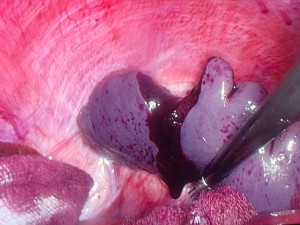

Esplenectomía laparoscópica por rotura de bazo traumática

El TAC abdominopélvico revela moderada cuantía de hemoperitoneo con avulsión del polo superior del bazo sin objetivarse datos de lesión del pedículo vascular principal.

Dada la estabilidad hemodinámica de la paciente y ante los hallazgos del TAC, se decide realizar esplenectomía laparoscópica.

Anatomía patológica: Fragmentos de parénquima esplénico con signos de rotura.